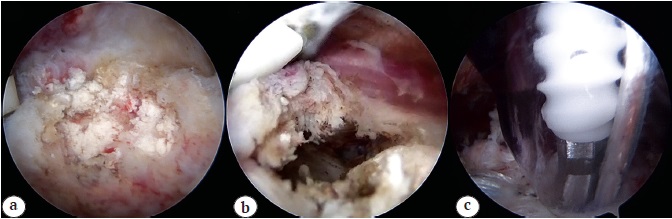

Fig. 2. Case 1. Arthroscopic removal of calcification with subsequent refixation of the rotator cuff: a — calcium deposit in the supraspinatus tendon; b — calcium deposit removed, partial tear of the supraspinatus tendon; c — installation of a fixing anchor